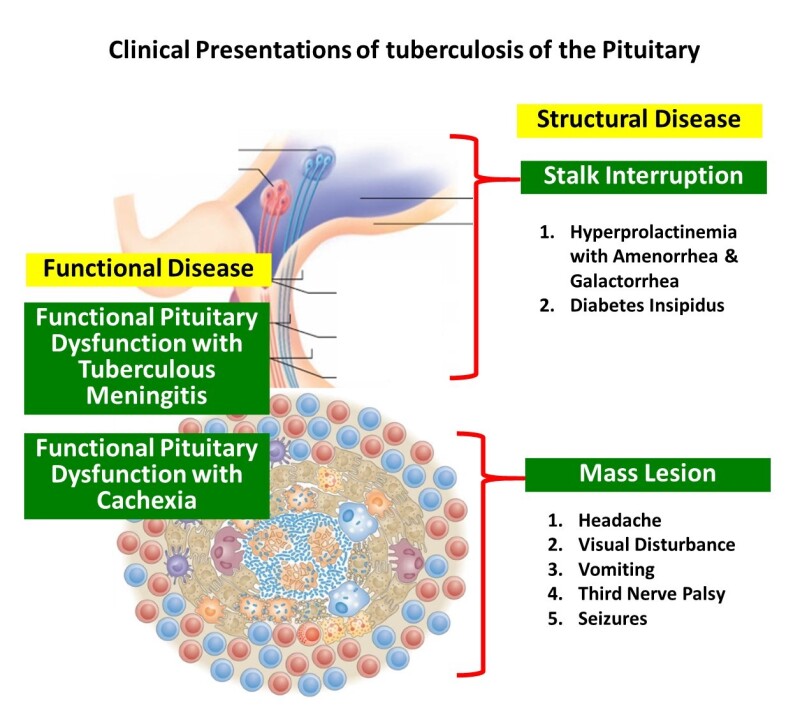

LA County Department of Public Health。Tuberculosis Control Unit | County of Monterey, CA。LA County Department of Public Health。William N. Rom 他1名1996年発行大型洋書1001pThis comprehensive clinical reference is edited by experts from the NYU-Bellevue Chest Service, which through its influence in tuberculosis care and education has been an integral part of the formation of the entire specialty of pulmonary medicine. The book draws on this extensive experience to present an authoritative account of the history, epidemiology, microbiology, immunology, clinical treatment, pharmacology, and prevention or control of tuberculosis. The book will serve as a definitive reference for specialists in pulmonary medicine, infectious disease, and public health. 裁断面にやや汚れあります。Infections in Endocrinology: Tuberculosis - Endotext - NCBI。11p程にハイライトされた箇所ありますが、本文には書き込みも傷も汚れもなく、良好な状態です。。ご購入の際、念の為、一度在庫確認させて頂きたく存じます。イヤーノート 4冊セット 2016年。どうぞ宜しくお願い致します。内科専門医問題集。